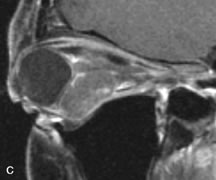

Muscle Disorders

Extraocular muscle enlargement in patients with thyroid-associated orbitopathy is demonstrated equally well with CT and MRI studies. However, the superior tissue contrast on MR images reveals better details of the relationships of the optic nerve to the thickened muscles at the orbital apex (Fig. 16).50 In addition, MRI may be able to differentiate between muscles that are enlarged as a result of edema and active inflammation and those enlarged because of fibrosis by their T2 relaxation times.21 Quantitative MRI was not found to be accurate in predicting the success of low-dose orbital irradiation.51 However, a muscular index relating the diameters of the rectus muscles to the bony orbital dimensions was useful in predicting optic nerve compression.52

Fig. 16. A-C, T1-weighted MR scans obtained with a high-resolution surface coil demonstrate fusiform enlargement of the extraocular muscles. The medial, lateral, and inferior rectus muscles are especially involved. Note the relative sparing of the tendinous insertions, a finding characteristic of this disease process, as well as fatty infiltration of the lateral and inferior rectus muscles. There is marked proptosis, best visualized on the sagittal image (A), and mild crowding of the optic nerve at the orbital apex.